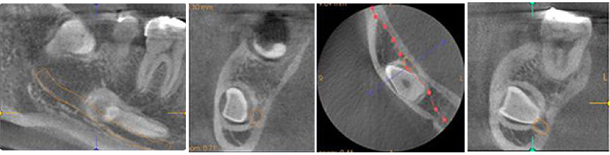

親知らずなど埋状歯(顎に埋もれた歯)を抜歯する場合、歯根(歯の根っこ)の位置や神経の位置を確認しておく必要があります。CTによる断層撮影はその位置関係を明確にでき、正確な審査・診断により、治療の安全性を高めます。

親知らずや位置異常歯、過剰歯を抜く場合でも歯の位置や向き、湾曲の程度また神経との位置関係が3次元的にわかることで、抜歯が手際よく安全に行えます。

いわゆる神経の治療ですが、根の先で神経が複雑に分岐していたり、根の先に病巣があり難治性の症例でも根先の状態を3Dで正確に審査する事で治癒率を向上させる事が出来ます。